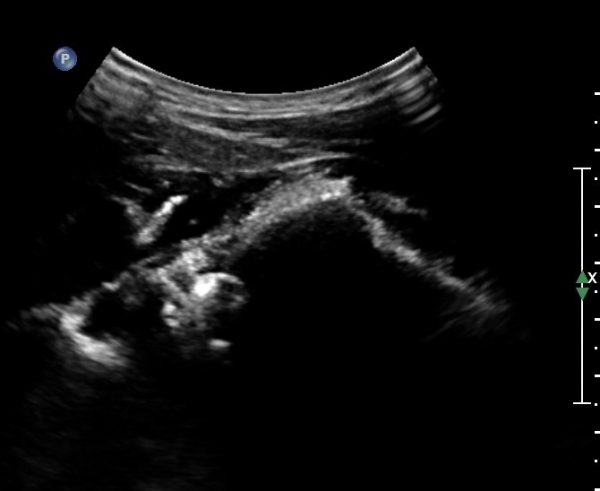

ÃÊÀ½ÆÄÀ¯µµÇÏ ÈíÀÎÄ¡·á Áß ÁÖ»ç¹Ù´ÃÀÌ ¼ö¾×³»¿¡ Á¤È®È÷ À§Ä¡ ÇÑ °ÍÀÌ °üÂûµÈ´Ù(»çÁø 7).

ÃÊÀ½ÆÄÀ¯µµÇÏ ÈíÀÎÄ¡·á ÈÄ ´ëºÎºÐÀÇ ¼ö¾×ÀÌ Á¦°Å µÈ °ÍÀÌ È®ÀεȴÙ(»çÁø 8).

º» Áõ·Ê¿¡¼­´Â 22G¹Ù´Ã·Î ÈíÀÎÀÌ ¾ÈµÇ¾î 18G ¹Ù´Ã·Î ¾à 5cc ¼ö¾×À» ÈíÀÎÇÏ¿´À¸¸ç

ÈíÀÎ ÈÄ Áï ½Ã Áõ»çÀÇ È£Àü°ú  ¼öµ¿Àû ³»Àü ½Ã ÅëÁõÀÌ ¼Ò½ÇµÇ¾ú´Ù.